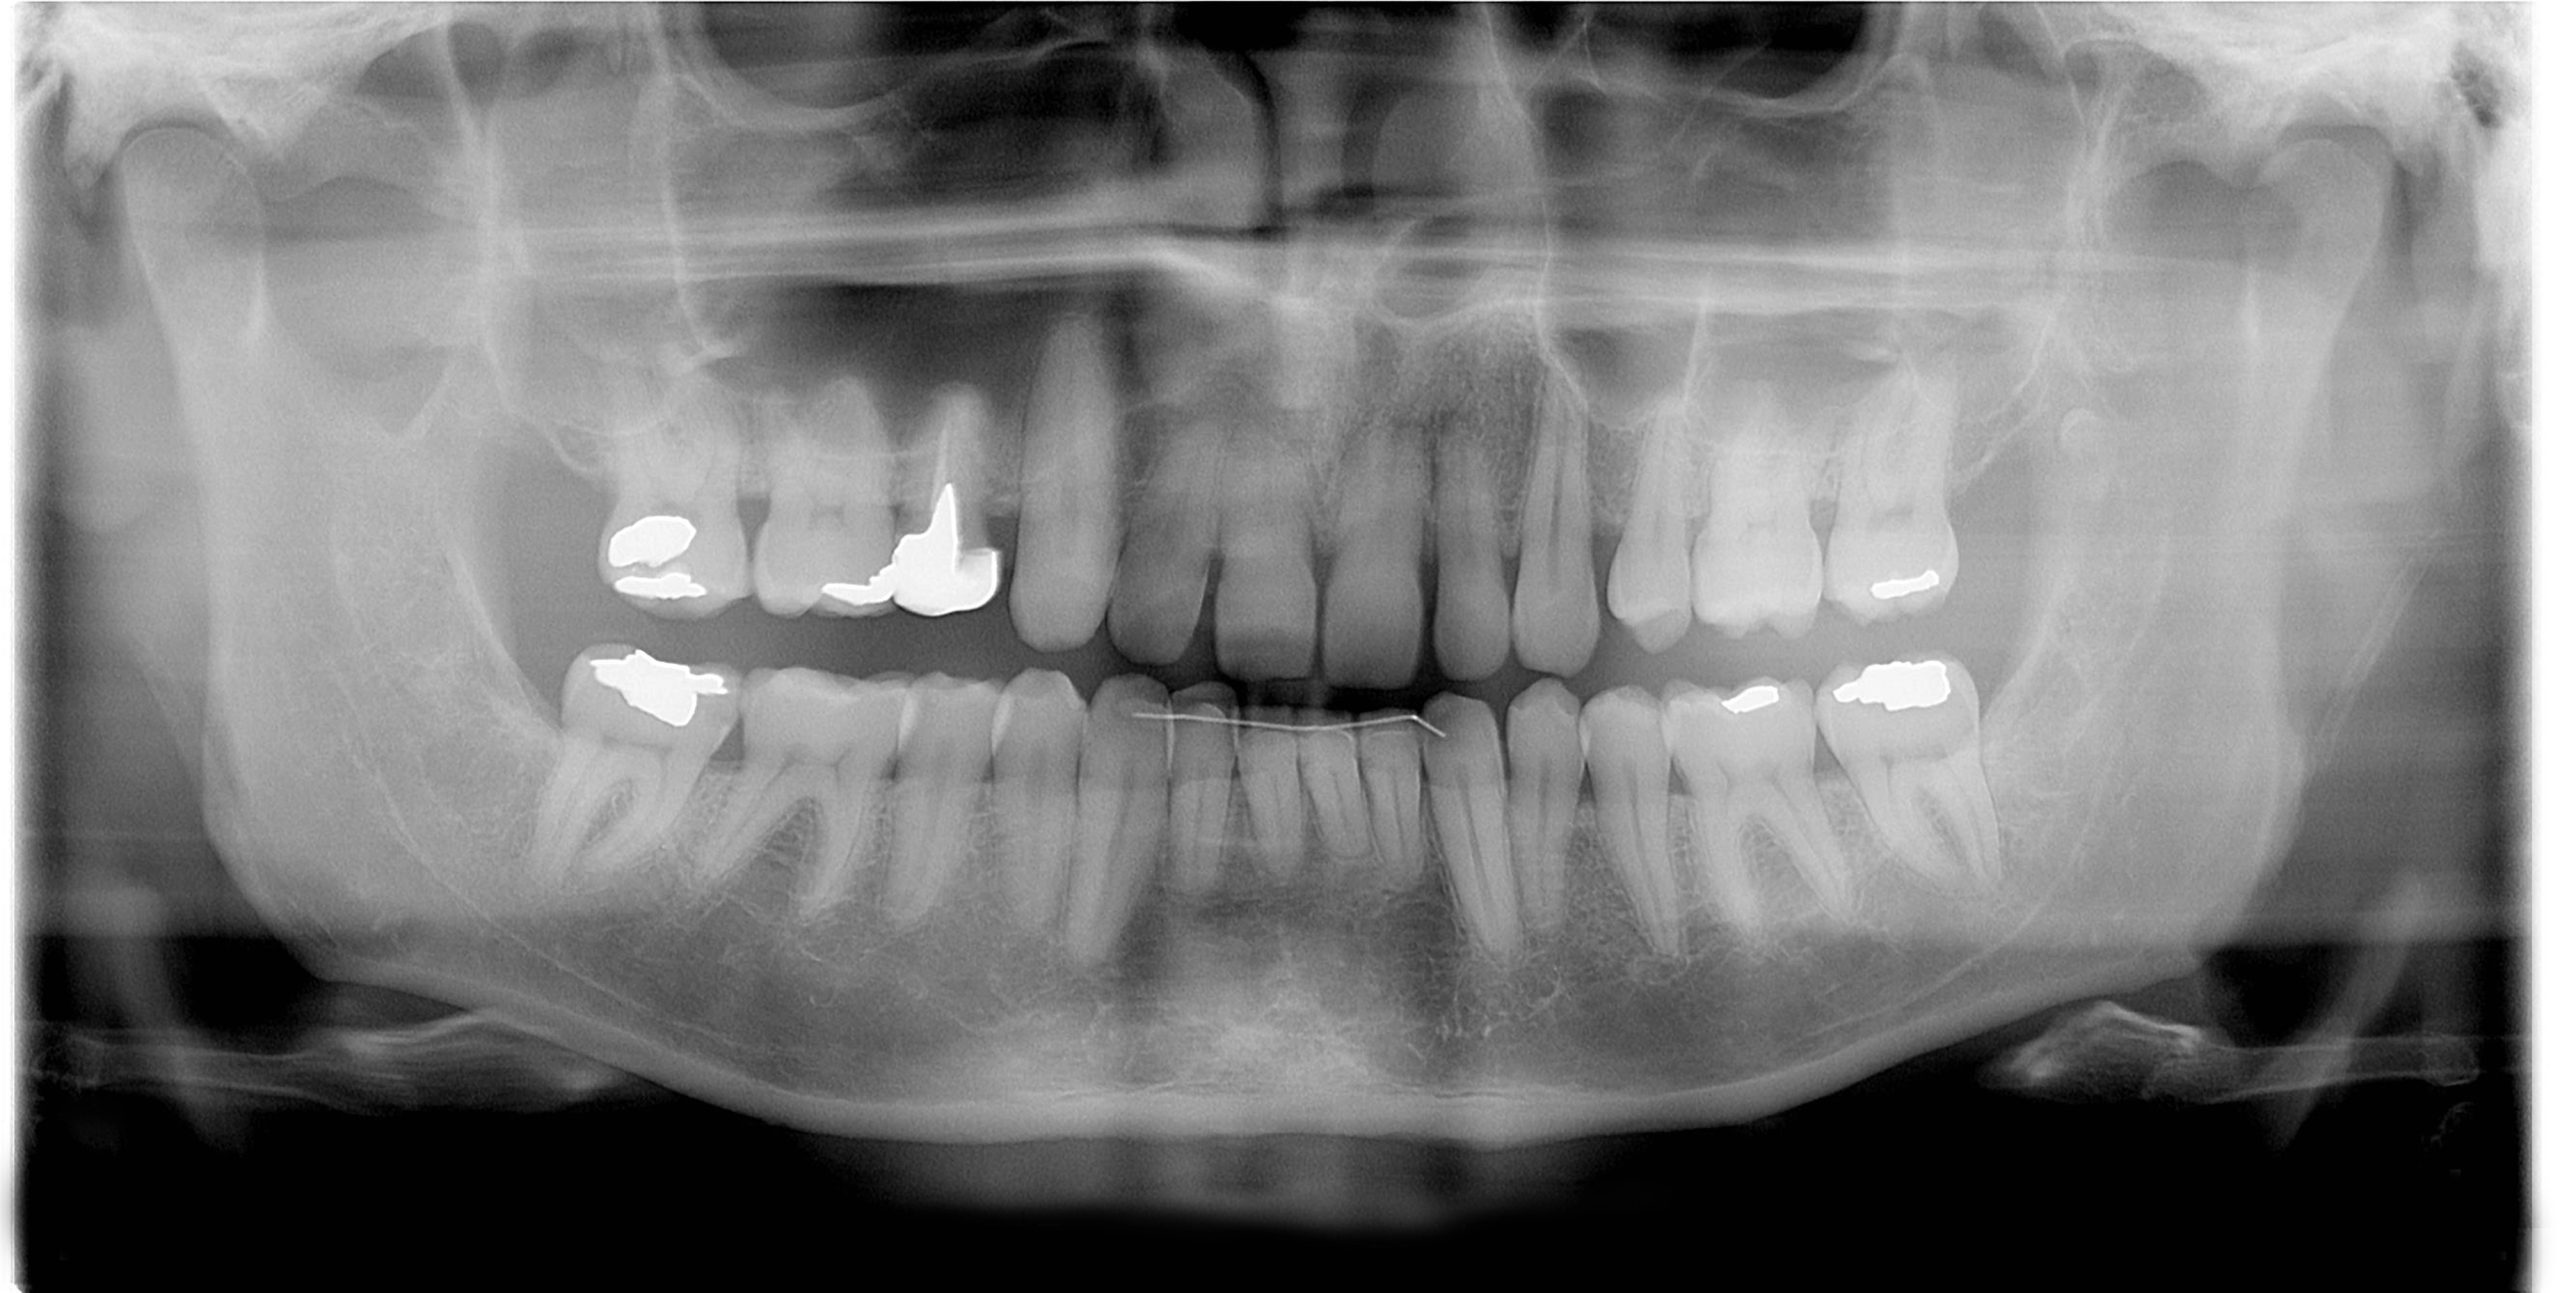

Dental Implants

PBM may help support healing after implant surgery by reducing inflammation and improving tissue recovery.

Tooth Extractions

After extractions, PBM may help reduce soreness and support healing of the surrounding tissues.

Gum Treatments

Patients with inflamed or sensitive gums may benefit from PBM as part of periodontal therapy.